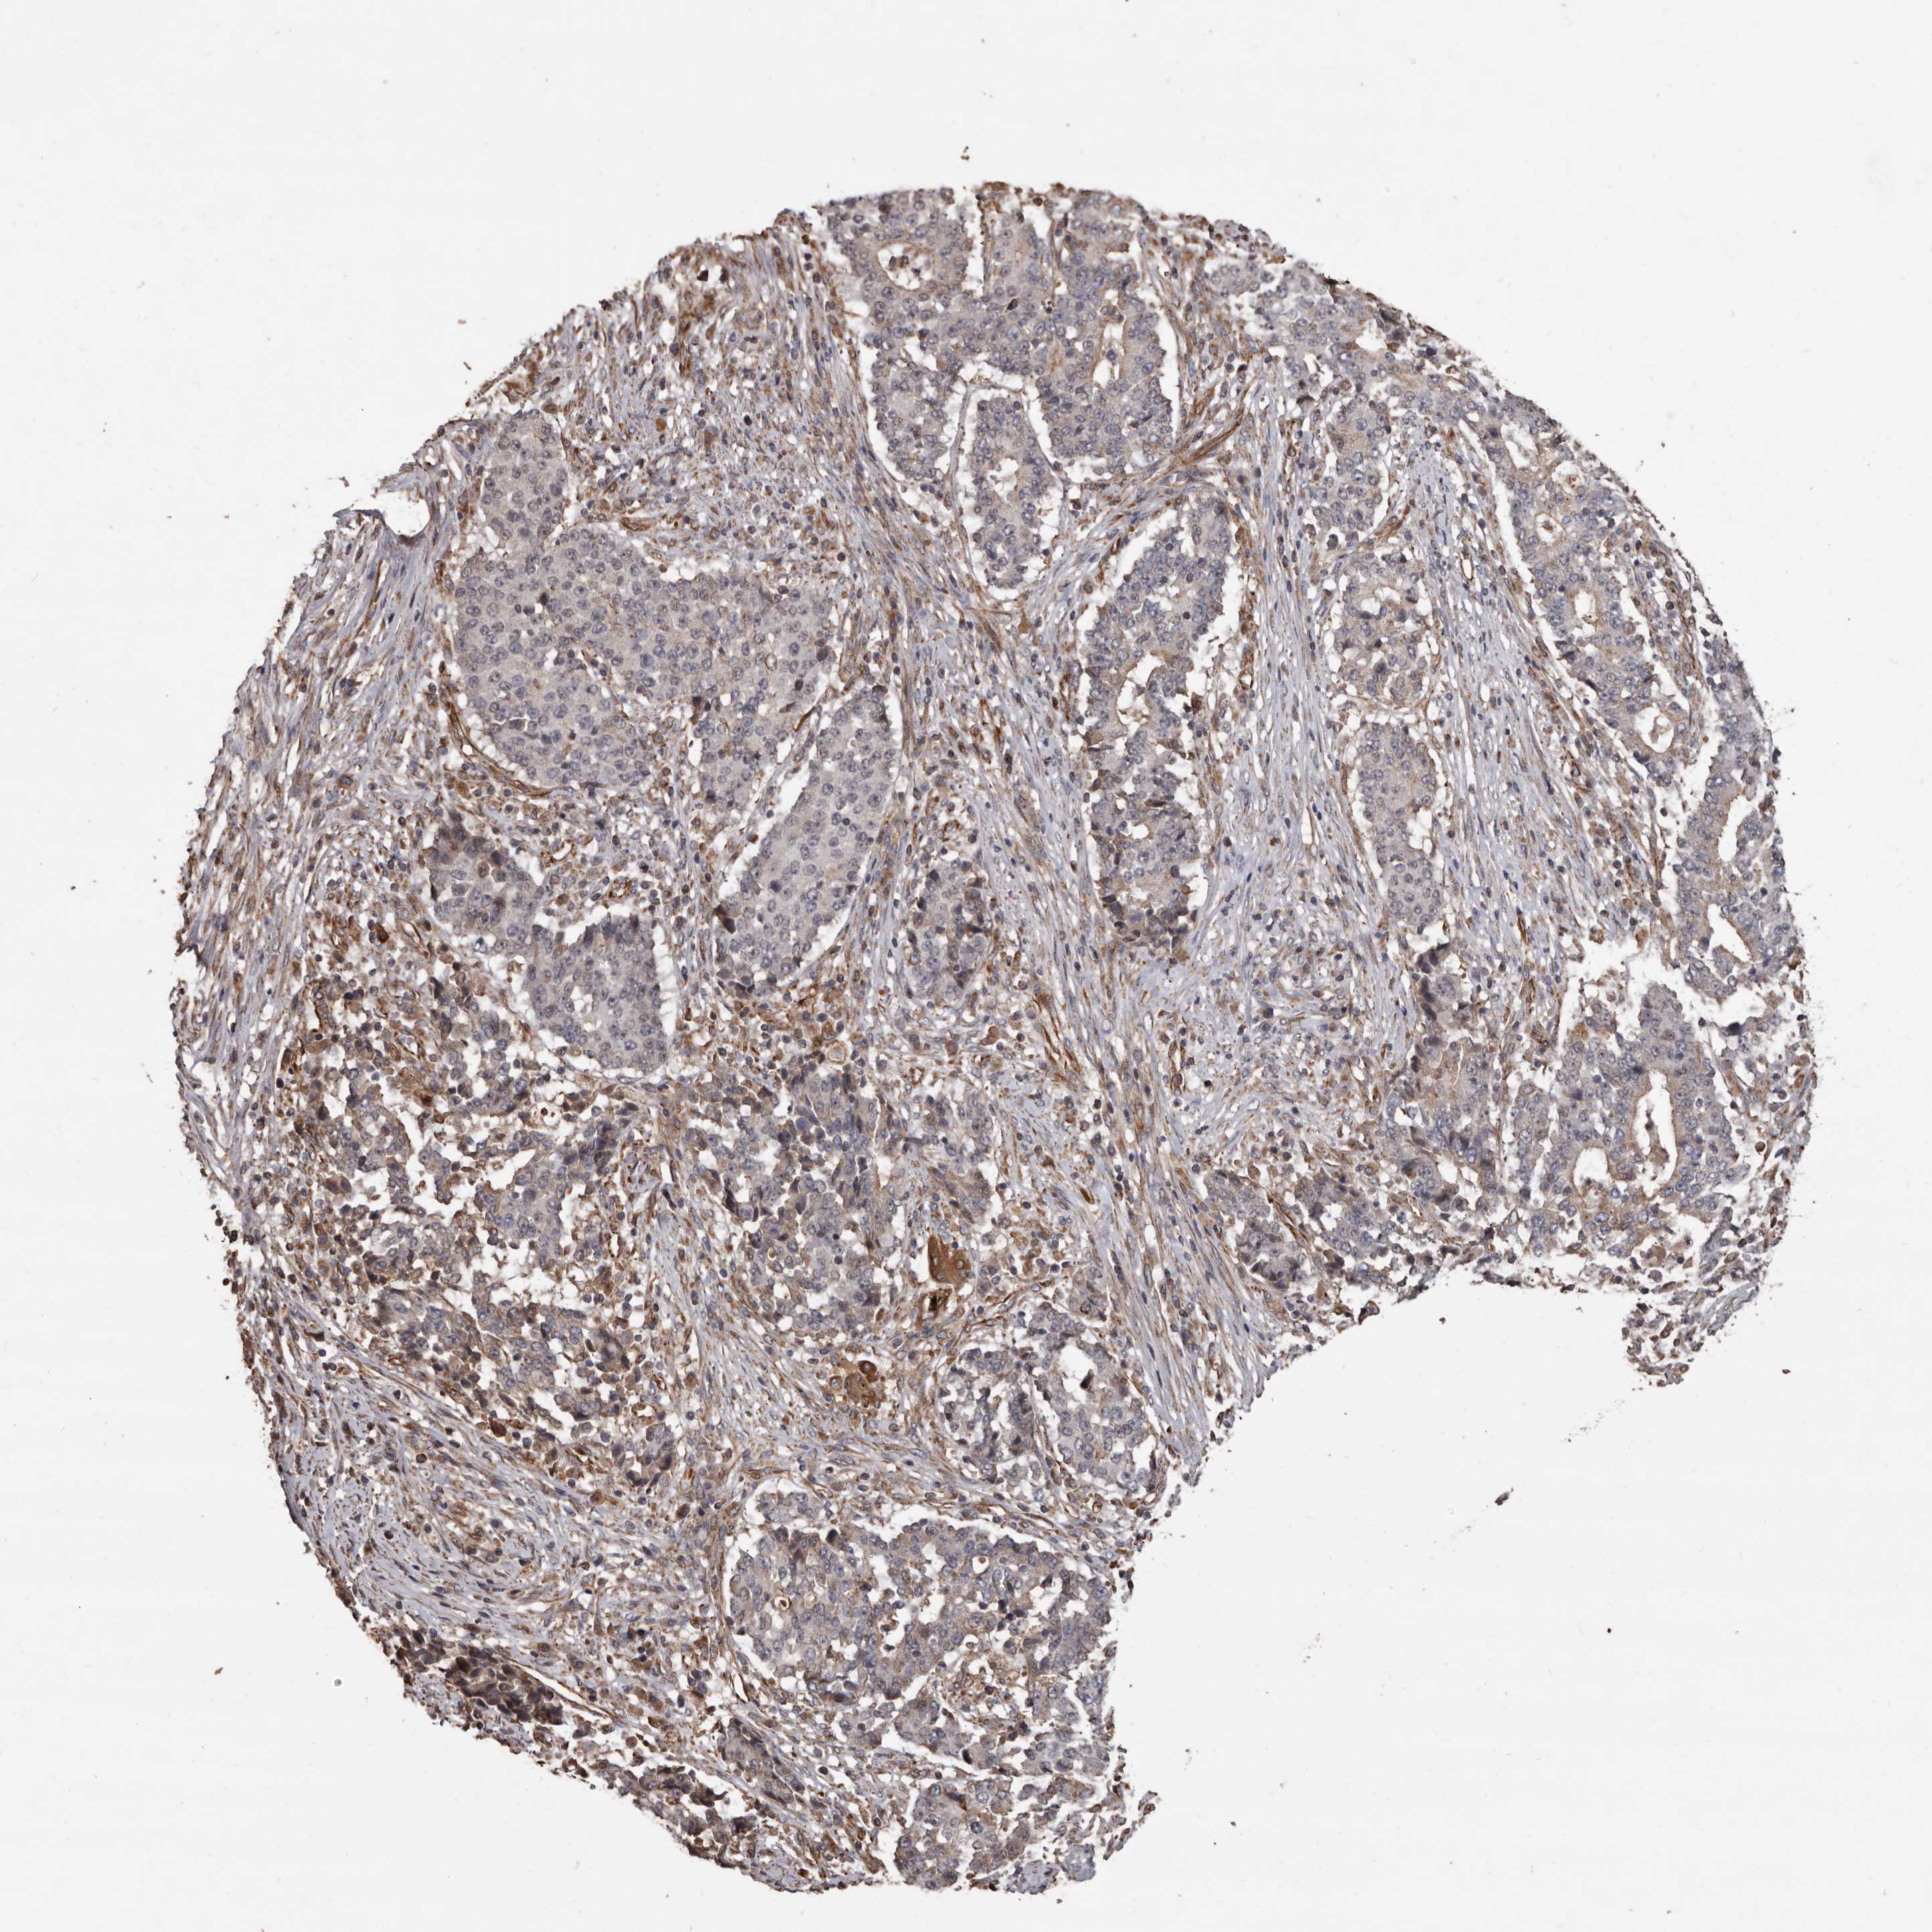

STOMACH CANCER - Protein expressioni

A mouse-over function shows sample information and annotation data. Click on an image to view it in a full screen mode. Samples can be filtered based on level of antibody staining by selecting one or several of the following categories: high, medium, low and not detected. The assay and annotation is described here.

Antibody stainingi

Antibody staining in the annotated cell types in the current human tissue is reported as not detected, low, medium, or high, based on conventional immunohistochemistry profiling in selected tissues. This score is based on the combination of the staining intensity and fraction of stained cells.

Each image is clickable and will lead to virtual microscopy that enables deeper exploration of all samples and also displays staining intensity scores, fraction scores and subcellular localization as well as patient and tissue information for each sample.

Antibody HPA029455

Staining

High

Medium

Low

Not detected

Intensity

Strong

Moderate

Weak

Negative

Quantity

>75%

75%-25%

<25%

None

Location

Nuclear

Cytoplasmic/membranous

Cytoplasmic/membranous,nuclear

Adenocarcinoma, NOS